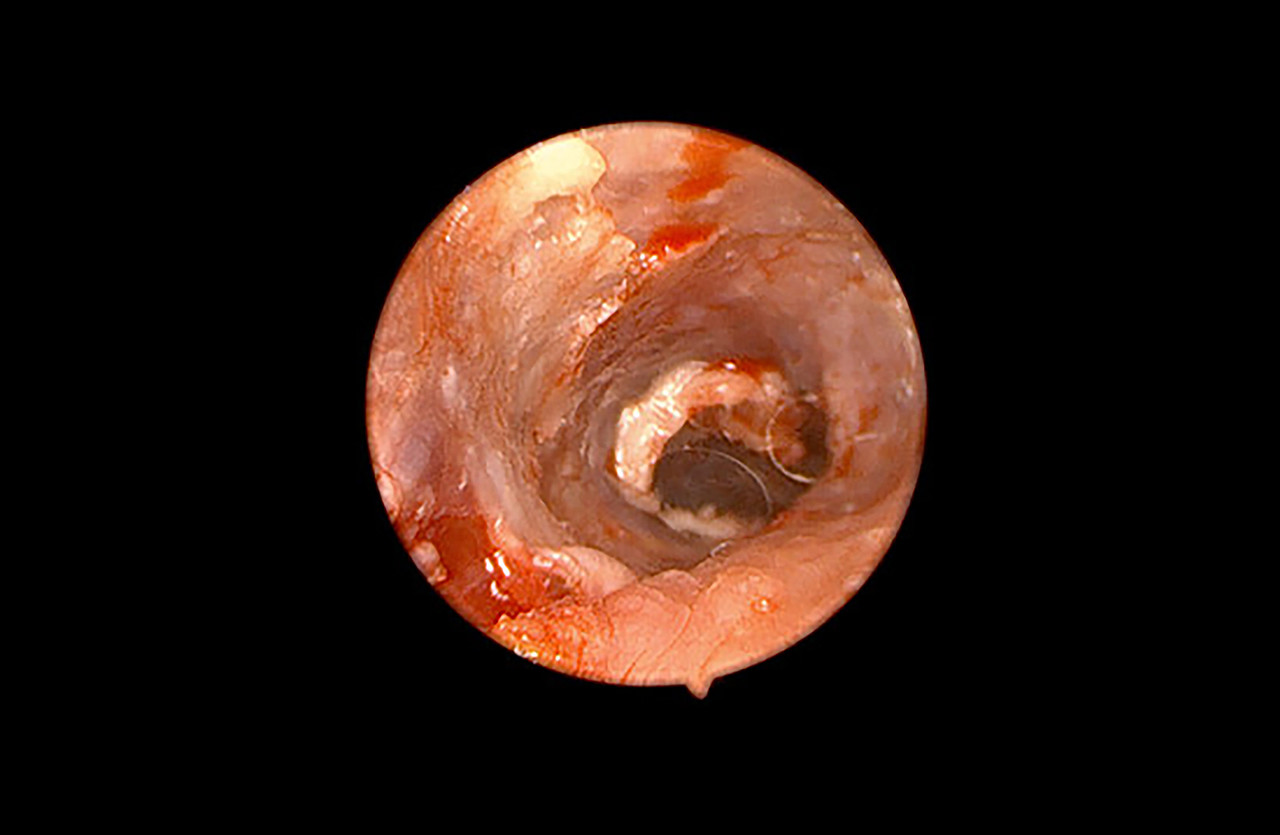

내시경

외부 절개 없이 체내에 고화질 내시경 카메라를 삽입 필요한 수술과 검사를 할 수 있습니다.

내시경 진료 중에는 움직임을 최소화해야 하기 때문에 마취가 필요할 수 있습니다.

안정된 후 체내에 내시경을 삽입하여 실시간으로 영상을 확인하며 필요한 수술 및 검사가 진행됩니다.

위/식도 이물 제거, 위/십이지장 조직검사, 폴립 제거, 대장 검사, 조직검사

이도(귀) 검사, 폴립 제거

비강(코) 검사, 비강내 이물 제거, 비강 조직검사

기관/기관지 검사, 기관/기관지 이물 제거